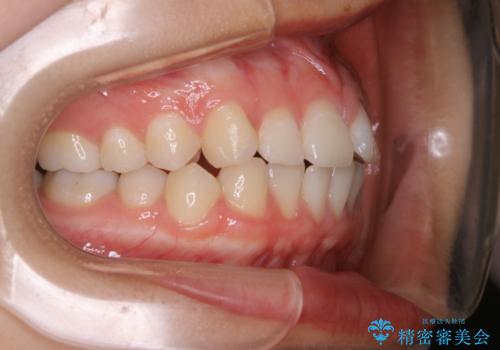

前歯のがたつきをインビザラインで治療

- 上下前歯のがたつきが気になるとの事で来院された患者様です。がたつきの程度が軽度であったため、インビザラインライトにて治療をおこないました。

がたつきの程度が軽度であったことと、インビザラインを正しく装着して頂けたことで短期間で治療終了することが出来ました。